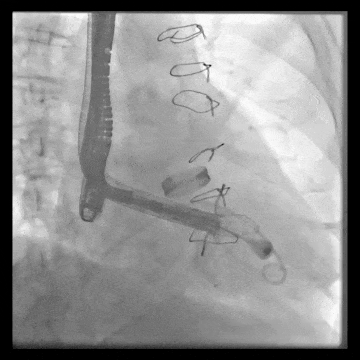

術中DSA顯示起搏器導線的干擾,右心室造影確定瓣環(huán)位置,操作空間小